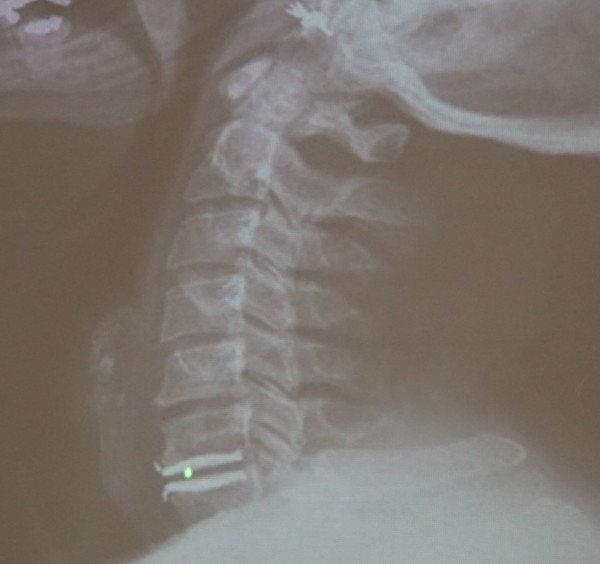

Feb 26, 21 · 颈椎压迫神经的症状分为压迫神经根和颈髓两方面。 颈椎压迫神经根的症状有:1、疼痛,一般表现为自颈部向上肢的放射性疼痛;2、感觉障碍,受到压迫神经根在上肢的支配区出现麻木、痛觉过敏、感觉减退等症状;3、肌力改变,早期肌张力亢进,晚期肌张力减弱,肌肉出现萎缩。Nov 08, 11 · 颈椎病吃药只是缓解作用,要除根的话建议您还是接受正规的治疗,最好是保守治疗,您与眩晕的情况的话应该属于脊髓型的,最好不要再耽误了,我们是通过中医手法复位正骨后(正骨12周,每隔一天一次,30分钟每次)改变压迫神经的关节位置使其不再压迫Aug 23, 19 · 虽然说确实有压迫神经的可能,但依然只是猜测,目前已有的检查并不能确诊! 患者需要做一个颈部核磁,这个检查是很有必要的,不光是确诊,更是未来治疗的依据,我们需要通过核磁更为详细的了解患者病情,病变位置、神经压迫程度进行综合考虑,对于此类患者来说,治疗方式有很多,作